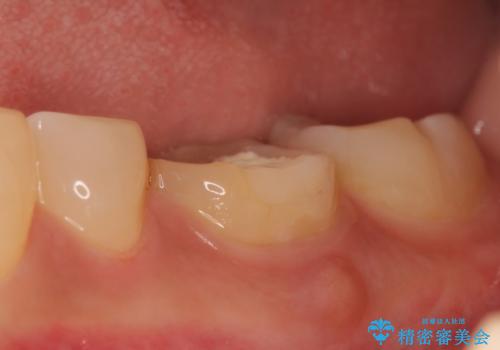

検査の結果左下6は神経が死んでいたため、根管治療を行いました。

その後症状の緩解を確認後、オールセラミッククラウンによる補綴を行いました。

今回用いたオールセラミッククラウンはジルコニアフレームという白い素材の上にセラミックを盛っているため、審美性が非常に高いのが特徴です。

また、ジルコニアは人工ダイヤモンドの材料にも使われているほど高い強度を持っており、そのためオールセラミッククラウンは審美性だけでなく、奥歯やブリッジの補綴も可能とするクラウンです。